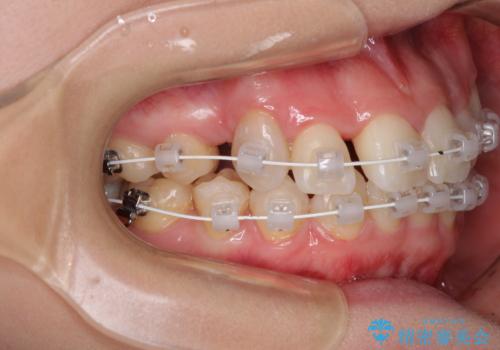

上顎の八重歯と下顎前歯の欠損 ワイヤー装置による抜歯矯正

- 上顎の八重歯を気にして来院された患者様です。

診察したところ、下顎前歯が2本欠損していたため、上下のバランスを取りながら八重歯を改善するため、上顎左右第一小臼歯2本を抜歯することとしました。

下顎左右大臼歯の歯根部に病変があったため、矯正治療前に根管治療を行い、矯正治療後にセラミッククラウンによる補綴治療を行うこととしました。

下顎前歯と本来抜歯矯正で抜歯する歯とは大きさが異なるため、仕上がりの咬み合わせは理想的なものとはなりませんでしたが、気になっていた八重歯はきれいに改善することができました。